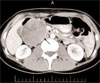

A CT scan with contrast of the abdomen reveals a well-defined mass arising from the inferior aspect of the head of the pancreas at the Oddi sphincter (Figure 1). The tumor has both solid and cystic components, with diffuse, inhomogeneous enhancement and no evidence of calcification. The mass is associated with mild pancreatic and biliary ductal distention. No other abnormalities are noted within the abdomen or lung bases.